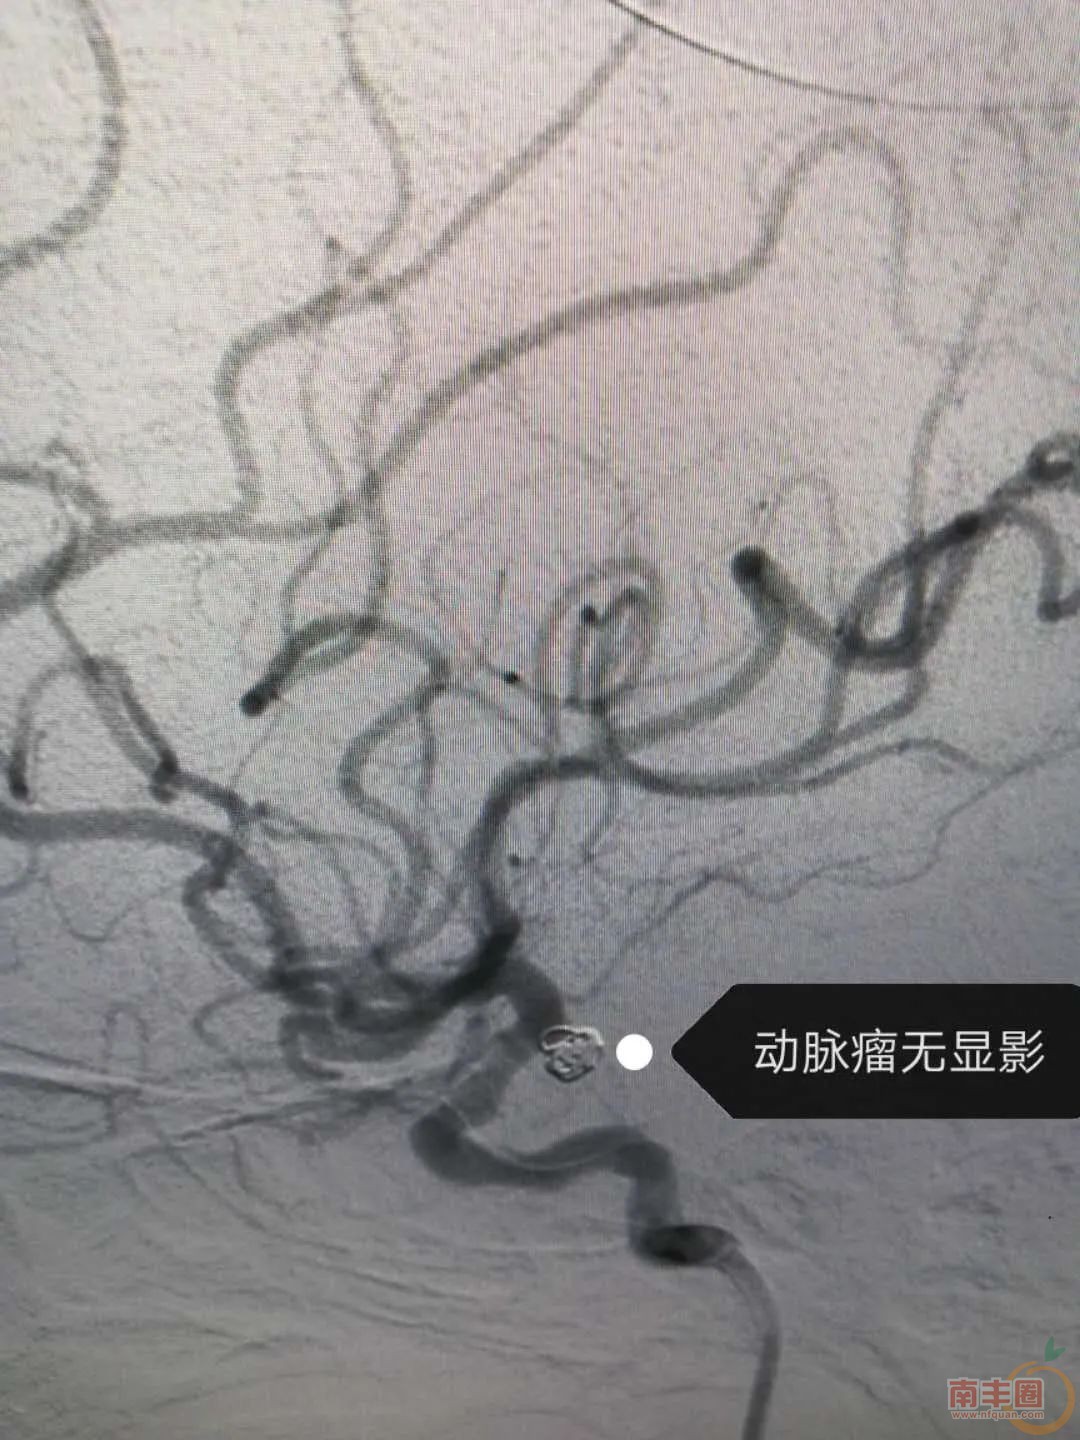

患者胡某、女、74岁,因反复头晕入院,磁共振检查发现颅内动脉瘤,于6月28日局麻下行脑血管造影术,提示:左侧后交通段窄颈动脉瘤。神经医学科主任吴宾和副主任胡亮向患者家属讲述了患者的病情以及治疗方法,经过患者家属的同意,决定行颅内动脉瘤介入栓塞术。于7月1日,在南昌大学第二附属医院介入治疗专家的指导下,在介入导管室、麻醉科等相关科室通力配合下全麻行经导管左侧后交通动脉瘤单栓术,历经一个小时的努力,手术顺利,患者神志清醒,无神经功能缺失。

影像

资料